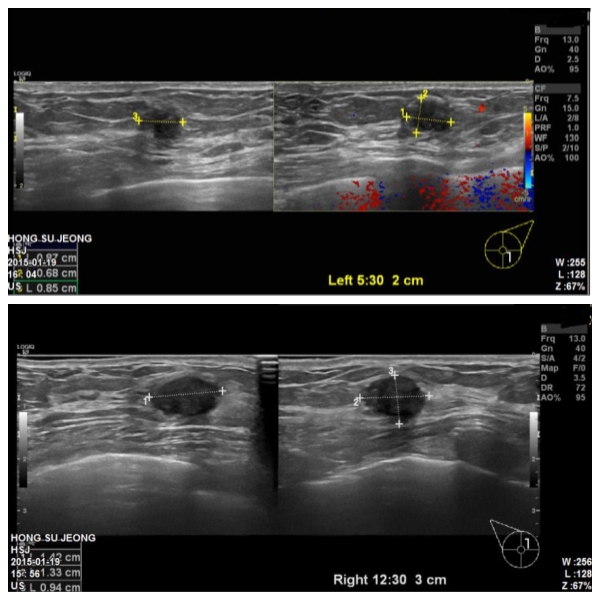

양측유방에 혹으로 내원하신 73세환자분이십니다.

본원에서 유방초음파 후 양측유방에 혹 조직검사 시행하였고

양측유방모두 침윤성 유방암진단되었습니다.